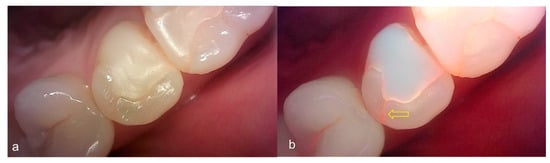

The values of the QLF parameter according to the value classified based on the QLF criteria were significantly different (Table 2). The cut-off value of |ΔFmax| and ΔRmax for determining a crack (QLF criteria scores 0 and 1 vs. 2) was 20.80 and 39.00, respectively. In addition, the AUROC of QLF parameters were similar (0.83, 0.82) (Table 3). Representative images of QLF and bitewing radiograph of dental cracks are shown in Figure 9 and Figure 10.

Figure 9.

Cracks: (a) white-light image of QLF, visual examination score 0 (No detectable crack line) on #15; (b) fluorescence image of QLF, QLF caries score 1 (fluorescence loss and red fluorescence present as a line in a crack site) on #15.